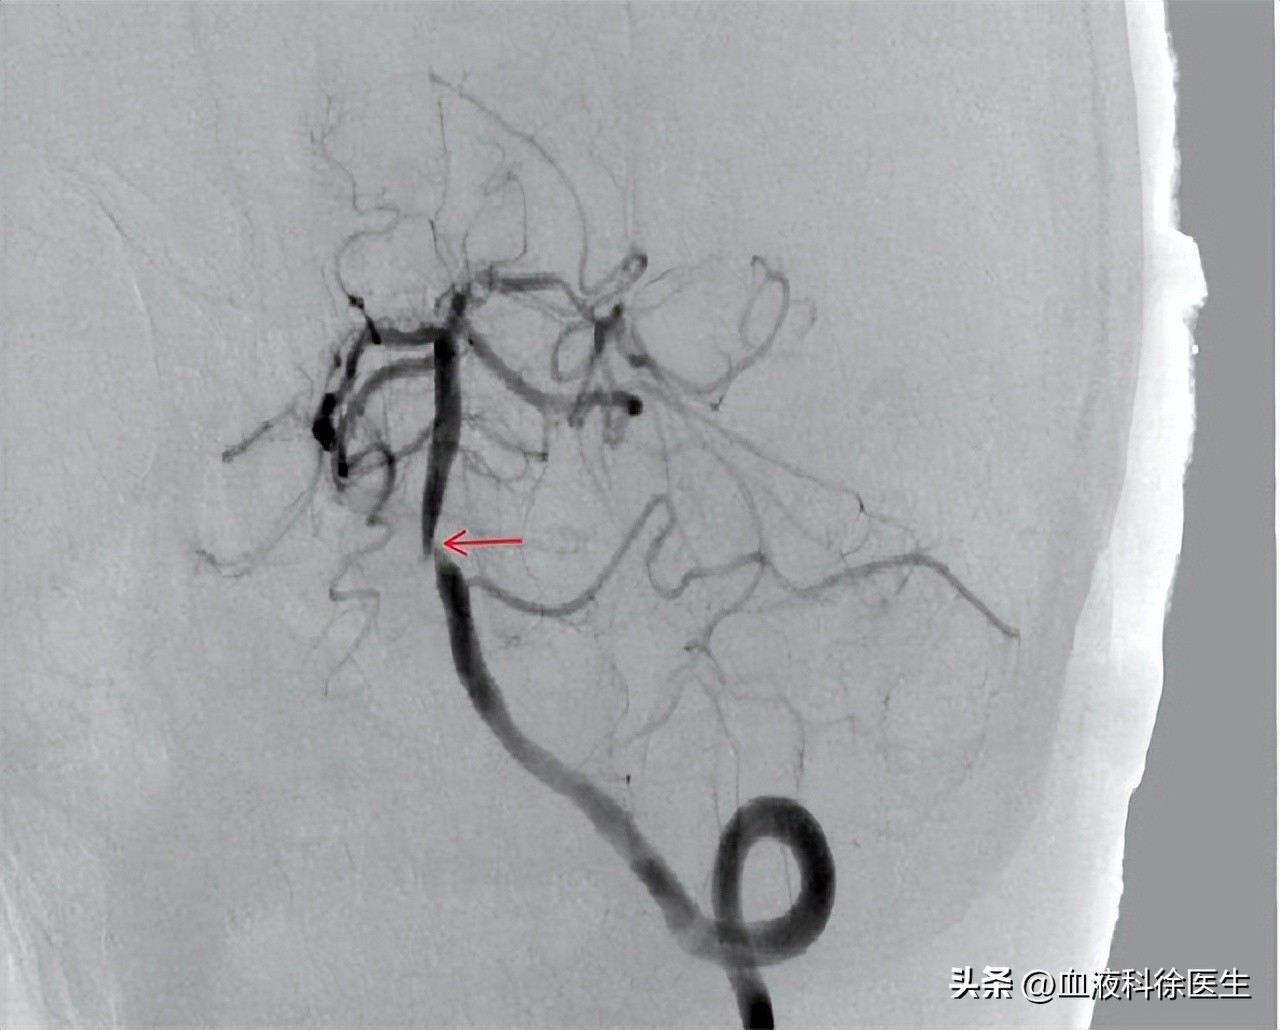

到了医院,医生给吴爷爷进行了血管造影的检查,发现老人家的 基底动脉 已经堵塞了近 90% ,如果再晚来一点很有可能就会发生脑梗死,危及生命。

医生解释道, 基底动脉是大脑的重要供血血管,主要负责供给脑干、小脑等, 脑干是重要的生命中枢,一旦脑干缺血,轻则偏瘫,重则昏迷、呼吸停止,短时间内就致命。儿子一听这话,不禁责怪吴爷爷就是平时老喝大酒,才得了这样的病。